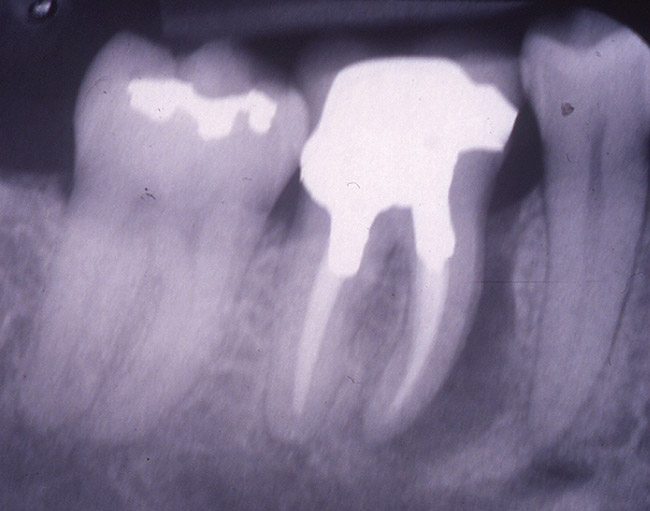

The patient was a 65-year-old healthy man who was referred for a periodontal evaluation of tooth No. 28. The patient presented with the chief complaint of pain and swelling in the lower right side of his mandible. Clinical examination revealed deep probing depth primarily (9 mm) on the distal-facial aspect of tooth No. 28. The tooth presented with grade 2 mobility. A periapical radio­graph of the tooth revealed the presence of a radiolucent appearance that was more significant at the midroot level (Figure 2A). The prognosis was determined to be "hopeless" because of a root fracture.

Figure 2a  A periapical radiograph of the tooth revealed the presence of a radiolucent appearance that was more significant at the midroot level. A root fracture was evident after flap elevation.

Figure 2a